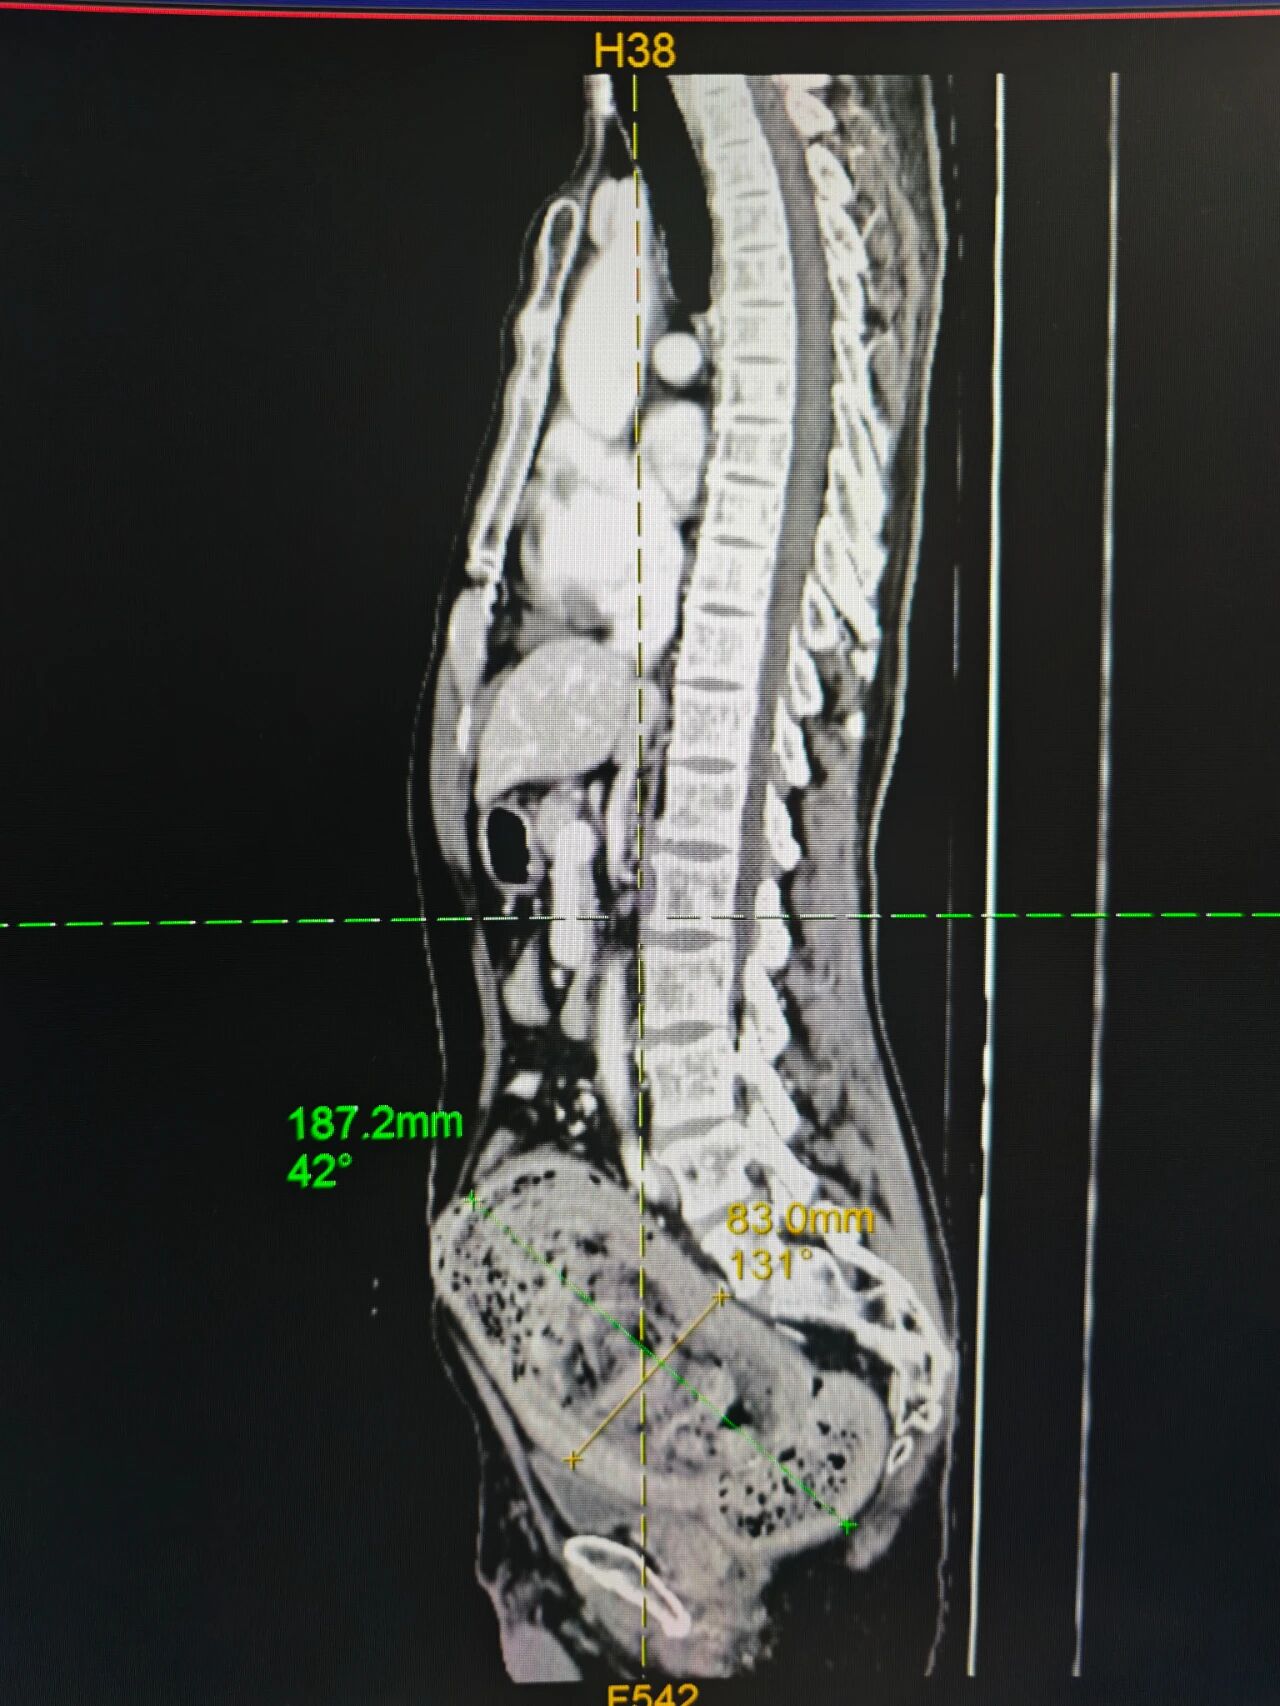

为求彻底诊治,患者慕名来到我院。入院后,完善的腹部CT检查结果令所有医生为之震惊:其造瘘远端肠管已极度扩张,形成一个巨大的囊状结构,尺寸约达20*10*10厘米,宛如一个充满隐患的“定时炸弹”,紧紧压迫着周围组织和脏器,这也是导致患者剧烈腹胀疼痛的根本原因。

图:巨结肠的冰山一角(上);肠内容物 (下)